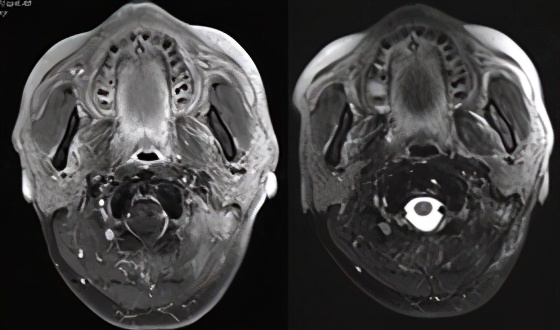

PD-1单抗联合化疗第一次影像评价(左:治疗前,右:治疗后2019.12)左颈部淋巴结稍有缩小

德瓦鲁单抗联合化疗第一次影像评价(左:治疗前;右:治疗后2020.5.11)

德瓦鲁单抗联合放疗后第一次评价(左:2020.5.11;右:治疗后2020.9)